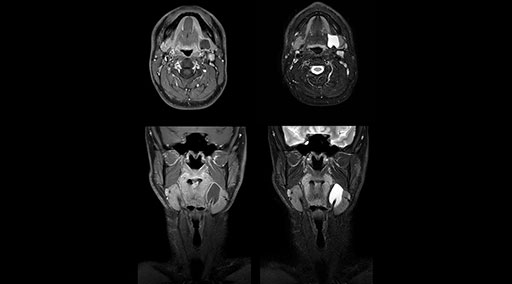

mDIXON TSE fat suppression helps DMG reduce repeats and supports diagnostic confidence

“Our DMG Lisle location includes a cancer center, so soft tissue neck scans, brachial plexus scans, and prostate scans are common. For these exams, mDIXON TSE provides excellent images with and without fat suppression all while helping us reduce repeats and work more efficiently,” Mr. Duffy says.

“With the 2-echo Philips mDIXON TSE the timing is short and the fatsat is very robust. The biggest thing is that you know your fat suppression will be good, even in thin patients or large patients that are off-center,” Mr. Sybesma says.

“Since we work in fixed time slots, not having to repeat scans is key for us,” Mr. Duffy adds. “With mDIXON TSE we get high quality results the first time – unless of course the patient absolutely jumps off the table. For us, that’s significant, because just a single repeat scan could put us behind schedule.

“mDIXON TSE raises our diagnostic confidence with its homogeneous

fat suppression. Neck exams and rheumatology patients are two examples where mDIXON TSE is especially useful,” Dr. Kaakaji says. “For us it’s also an efficiency boost in exams where we need pre and post T1-weighted images with great fat suppression.”